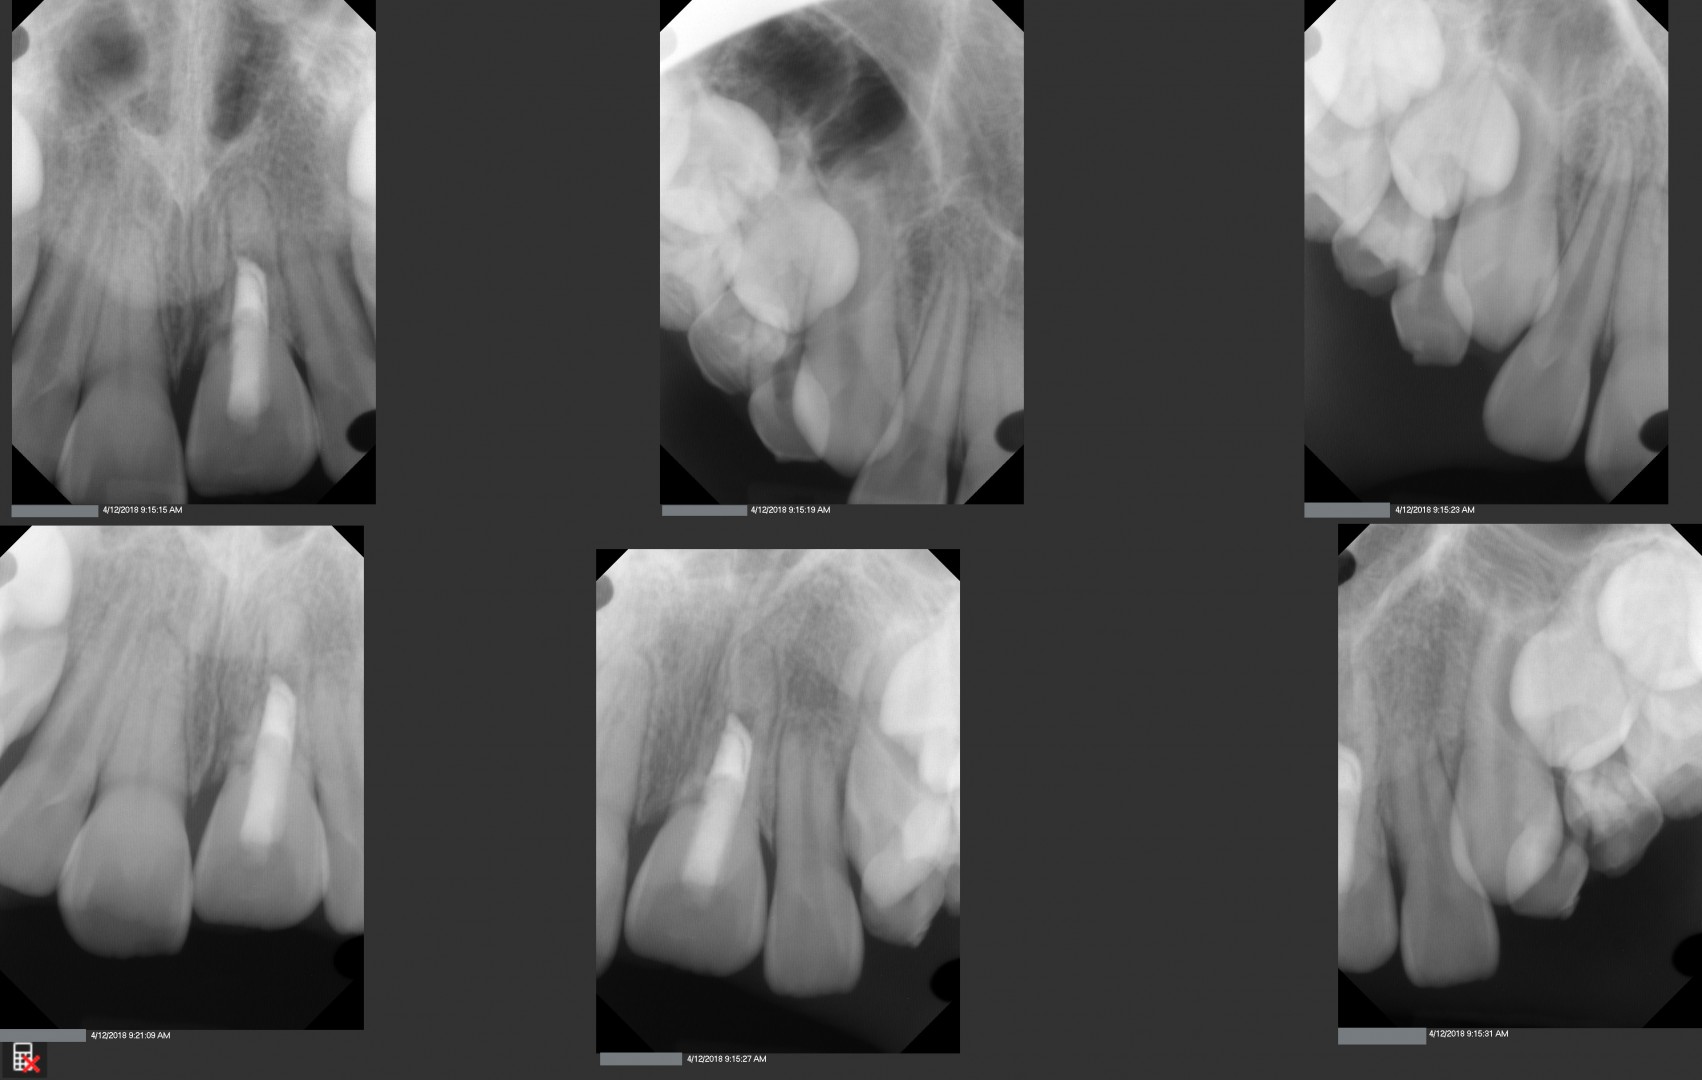

This is a 9yo girl with a high esthetic desire (wants to be a model/actor). She avulsed tooth #9 about 3 years ago, and she has been under treatment with other endodontists. I guess they attempted revascularization with MTA about year ago. #9 is ankylotic with a few mm’s infraposition. It is gray due to the MTA. #8 is slightly yellow/white due to calcification/obliteration but she says she feels cold testing and it is otherwise asymptomatic.